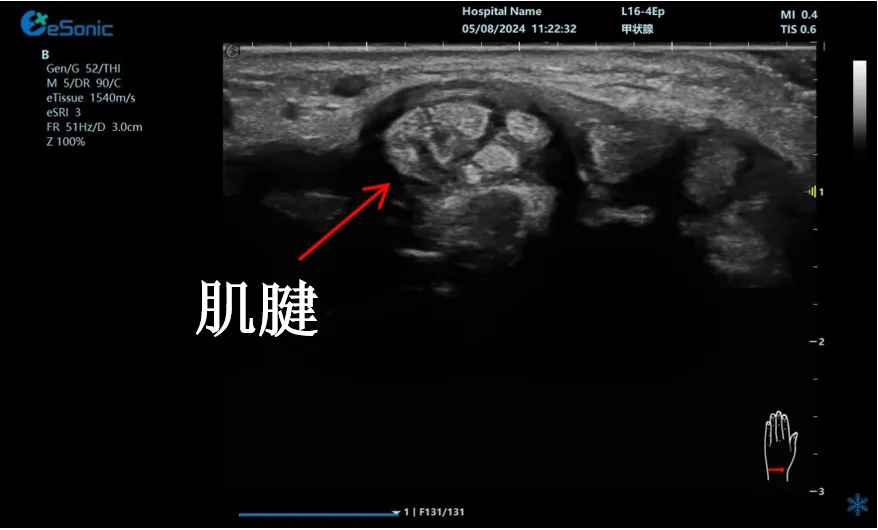

mFlow?技术在腱鞘炎诊疗中的应用

【背景】:左手腕关节第四腔室腱鞘炎。

【痛点】:普通彩色多普勒不敏感,只能看到细小点状血流,容易被忽略,难以进行分级诊断和疗效评估。

【方案】:银河官网医疗(ESI)超微血流技术可以看到腔室内肌腱周围环状血流,可充分提示:

1、处于炎症活动期;

2、根据血流进行分级诊断提示1级;

3、治疗后根据血流多少评估疗效(见右下图:治疗10天后复查超声,微血流图像血供消失)。